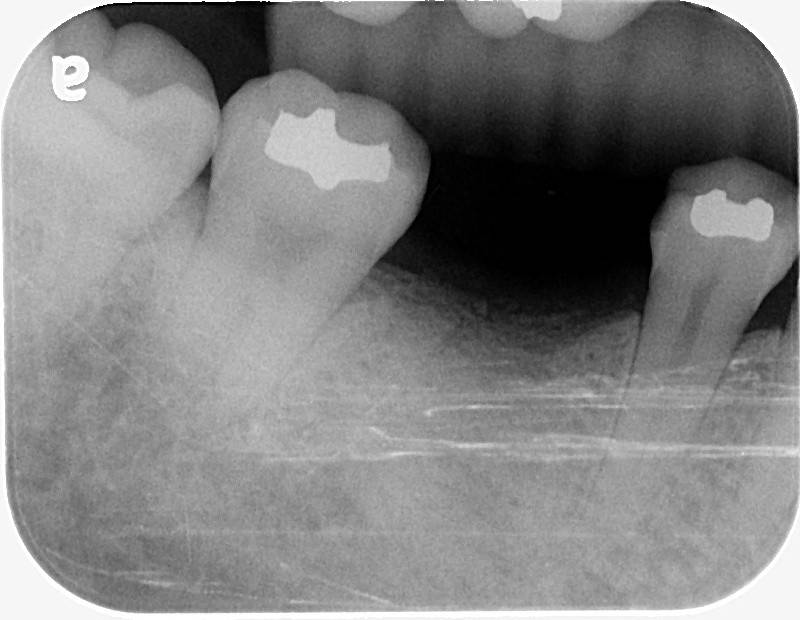

一開始只是單純的根管治療,

沒想到過程中發生器械分離的併發症,

導致牙根受損,最終只能走向拔牙 → 改做植牙 😵💫